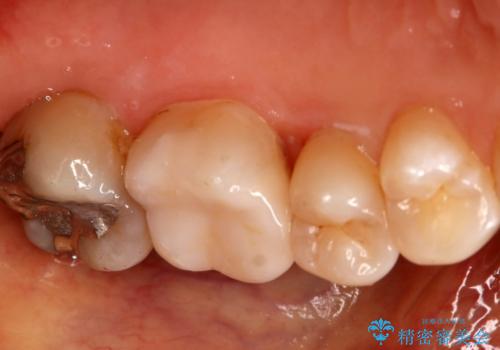

- 左上6番の銀歯をセラミックにしたいと希望され来院された患者様です。

切削量を考慮し、セラミックインレーを選択しました。

銀歯を除去したところ虫歯が深かったので、CRを詰めた上で形態を整えています。